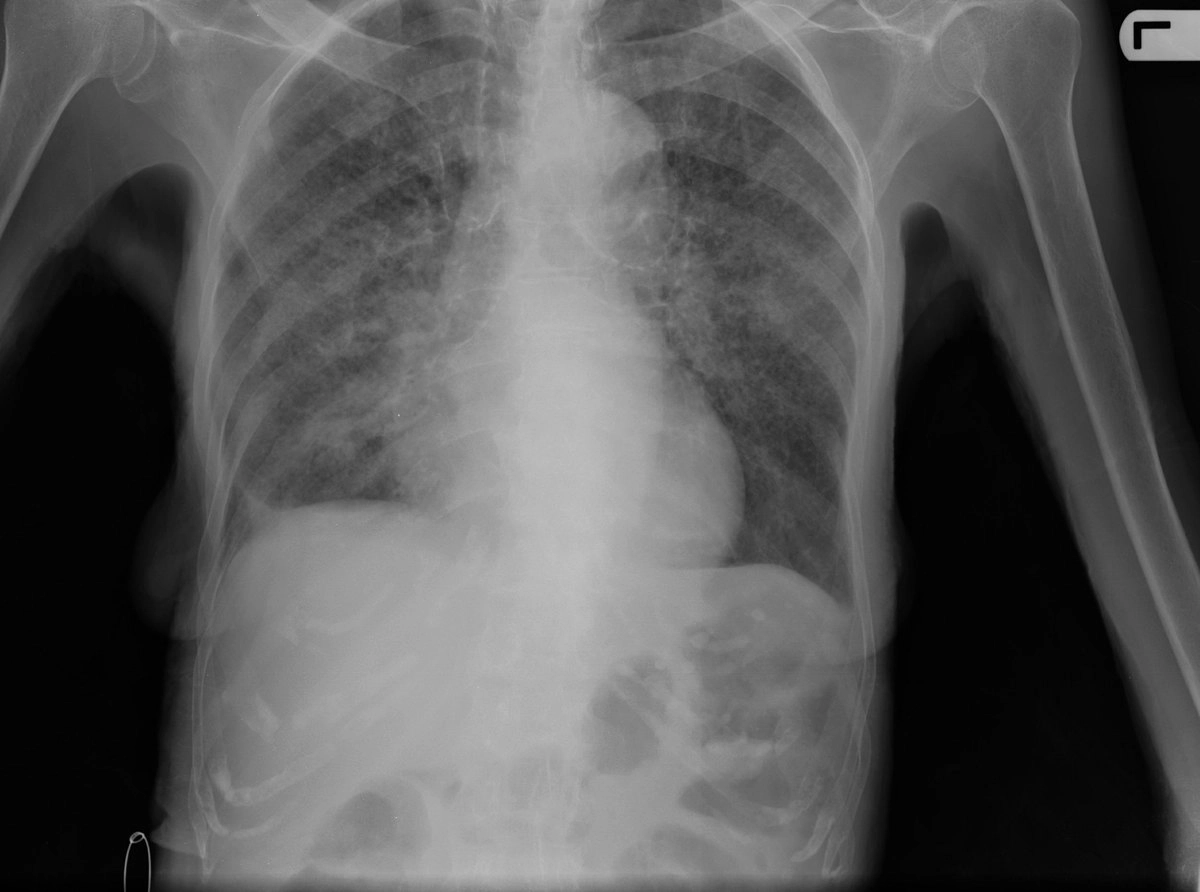

Самое страшное — туберкулез

Раз уж зашла речь про туберкулез, то расскажем и о нем. На «Матросске» под туберкулезных больных выделен отдельный корпус (третий) — «тубонар». На первом этаже содержатся здоровые заключенные, сосланные туда либо по собственному желанию, либо в связи со своей «блатотой», так как на «тубонаре» свое «положение» — полная анархия и вольность для заключенных. Пол там во многих камерах представляет собой просто землю, поэтому спрятать телефон и наркотики не составляет труда.

На втором этаже содержатся те, у кого закрытая форма туберкулеза, а на последнем — открытая. Последний этаж примыкал как раз к моему корпусу (четвертому), так что когда меня вызывали на следствие либо на свидание, то непременно приходилось проходить через ту часть «тубонара», где содержатся уже практически ходячие трупы. Можешь идти и вместе с таким «трупом» — ведь им тоже на следственные действия или к адвокату. Как правило, маски они не используют, как в связи с тем, что уже практически неотличимы от зомби из фильмов, так и с тем, что по своей природе — люмпены и элементы из социальных низов, поэтому чихать они хотели на всякие «меры предосторожности» и уж тем более на здоровье других заключенных. Хотя администрация и старается по максимуму изолировать их от других, но распространяется это только на совсем уж «трупов».

Нередко можно сидеть на сборке или в автозаке лицом к лицу с человеком, у которого выявлена закрытая форма туберкулеза. Конечно же, такой больной не откажет себе в удовольствии и покурить рядом с тобой, чтобы можно было насладиться дымом, выходящим вместе со всеми компонентами того, что творится у него в легких.

Да, можно повторять мантры про то, что это закрытая форма, нет причин для беспокойства, но откуда мне знать, в какой момент она может измениться и стать открытой? И не наступит ли этот момент сейчас, пока я нахожусь рядом с данным субъектом? Или что сотрудник не перепутал его «формы» и не посадил смертельно больного рядом со здоровыми людьми?